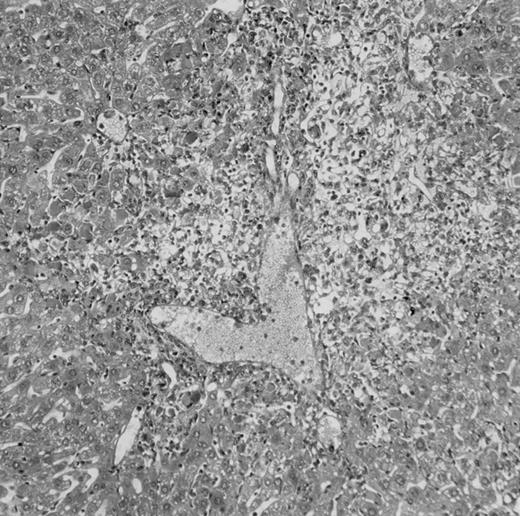

Histologic findings. Organs were collected at different times after BMT and tissue sections were stained with hematoxylin and eosin. Original magnifications for spleen (left) and liver (right) are ×40 and ×100, respectively. (A) B6 mice receiving FVB BM plus EpTK T cells. (B) Control group receiving BM only.

(C) B6 mice receiving FVB BM plus EpΔTK T cells and treated with GCV. (D) B6 mice receiving FVB BM plus EpΔTK T cells, treated with GCV, and developing a late onset GVHD (day 54).

FVB BM-grafted B6 mice: a model of lethal GVHD.We developed a model of GVHD resulting in 100% mortality soon after BMT using FVB mice, a strain not previously used as BM donors in experimental allogeneic BMT. We tested different combinations of recipient irradiation doses, as well as injected BM cell and CD3+ peripheral T-cell numbers. When 10-Gy–irradiated B6 mice were reconstituted with 107 FVB BM cells, we observed prolonged survival, whereas all ungrafted animals died before day 16 (Fig 2). In these conditions, more than 98% of splenocytes were of donor origin (Fig 3A). When 107 CD3+ peripheral T cells from mice of FVB genetic background were added to the FVB BMT, all animals died of GVHD between days 7 and 34 (Fig 2). Similar results were obtained using either PBS-treated mice receiving EpTK or EpΔTK peripheral T cells or GCV-treated mice receiving FVB nontransgenic peripheral T cells. Notably, this observation also indicates that both TK- and ΔTK-expressing T cells in the absence of GCV are fully competent to induce a lethal GVHD. Histopathologic examination of spleen and liver of these animals showed characteristic GVHD lesions such as (1) architecture disruption, necrosis, and congestion in the spleen; (2) hepatic periportal necrosis; (3) mononuclear portal infiltrates; and (4) endothelialitis of portal or centrolobular veinules (Fig 4A). By comparison, B6 mice receiving only FVB BM had a normal histology (Fig 4B).

Protection from GVHD was slightly less efficient in the group receiving EpΔTK CD3+ T cells. The survival rate was 79% at day 60 and 67% at day 120 (Fig 2B). However, two different outcomes must be distinguished. On the one hand, a majority of mice behaved as GCV-treated animals receiving EpTK T cells. They were apparently healthy, presented no skin lesions during a 120-day observation period, and showed complete donor-type hematologic reconstitution. There were no histological signs of GVHD in the spleen or liver (Fig 4C).

On the other hand, 5 of 19 mice exhibited signs suggesting the occurrence of a delayed GVHD (Table 1). Clinically, these animals presented weight loss and/or skin lesions on ears, neck, limbs, or abdomen, but only after day 40. In the absence of any further GCV treatment, 2 mice died 14 and 29 days after the occurrence of these signs (Table 1A) with histological signs of severe GVHD (Fig 4D). These results suggest that, in these mice, the 7-day GCV treatment was sufficient to prevent early, but not delayed GVHD.